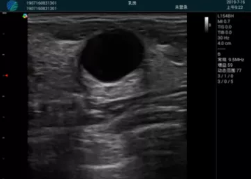

M20查看:囊內(nèi)回聲均勻,邊界清晰,囊壁光滑

M20引導(dǎo)抽吸術(shù)后囊腫消失,原區(qū)域空腔形成,脂肪層與腺體層架構(gòu)發(fā)生改變

甲狀腺囊性結(jié)節(jié),囊壁鈣化,透聲好

甲狀腺囊性占位